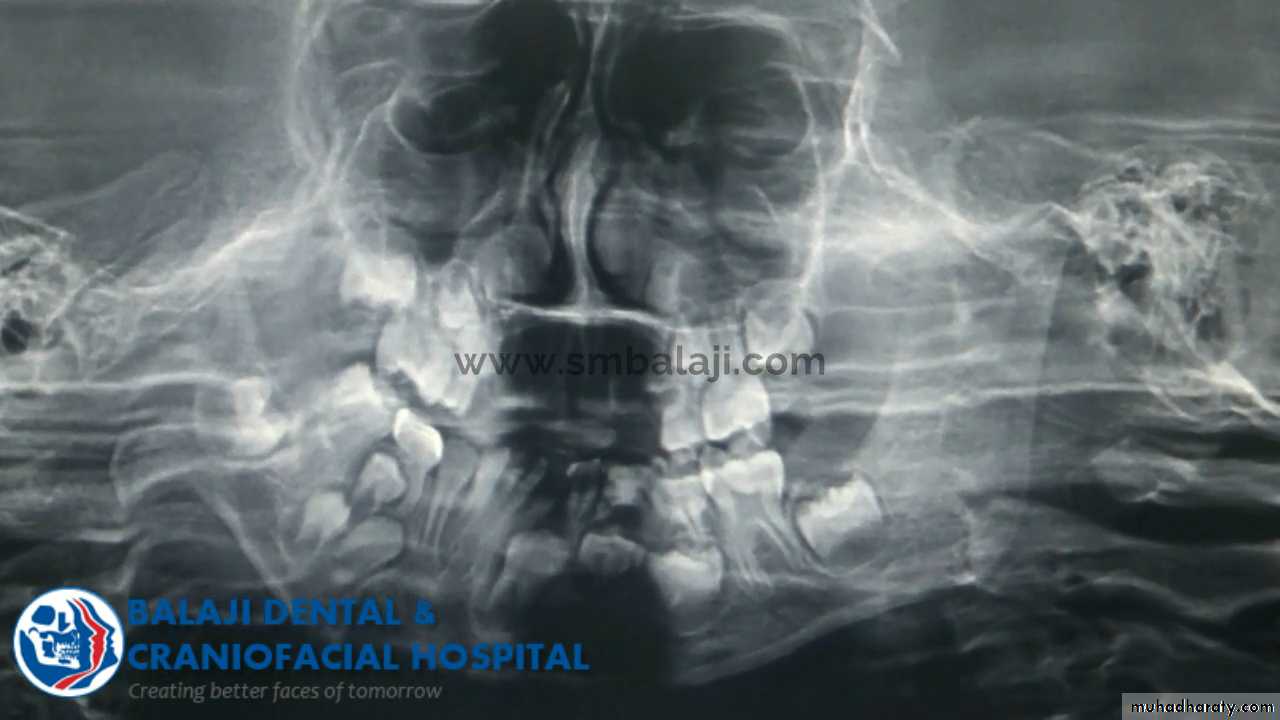

8Radiology

Radiography confirms a clinical diagnosis.The condyle may translate beyond the articular eminence normally, without a dislocation, so clinical information is essential. The condyle will be anterior and superior to the ‘summit’ of the articular eminence.

Dislocation

NB. Normally: the condyle may be translated anterior to the eminence as far as 5 mm.Dr. Mohammed Amjed Alsaegh, 2021